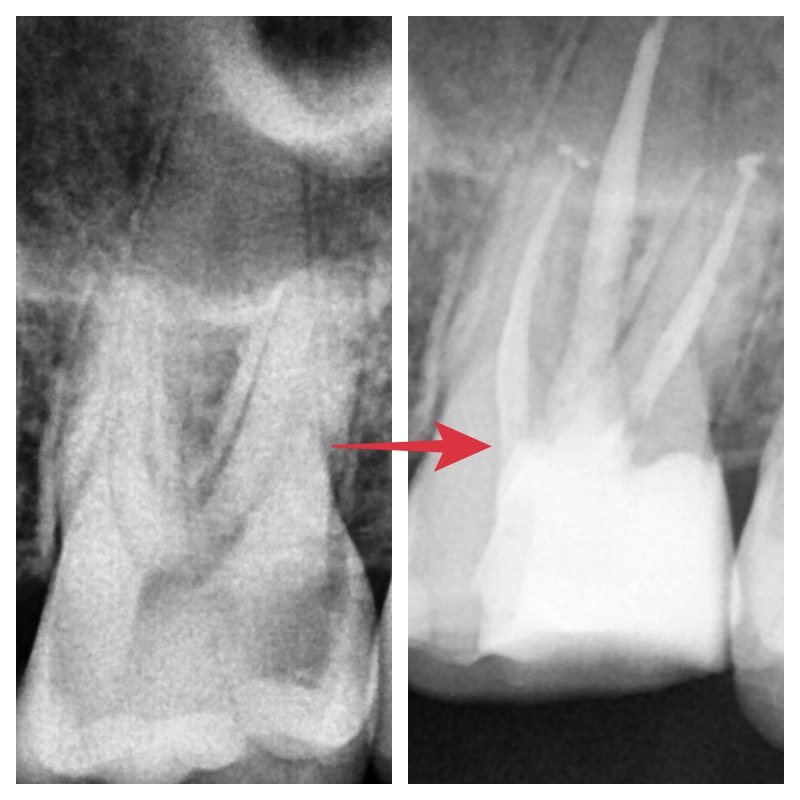

겉에서는 안쪽이 살짝 어둡게 보였지만

엑스레이상에서는 이미 신경까지 충치가 진행돼있었습니다

통법대로 근과 내부 세척하고 깨끗하게 충천까지 완료한 사진입니다.